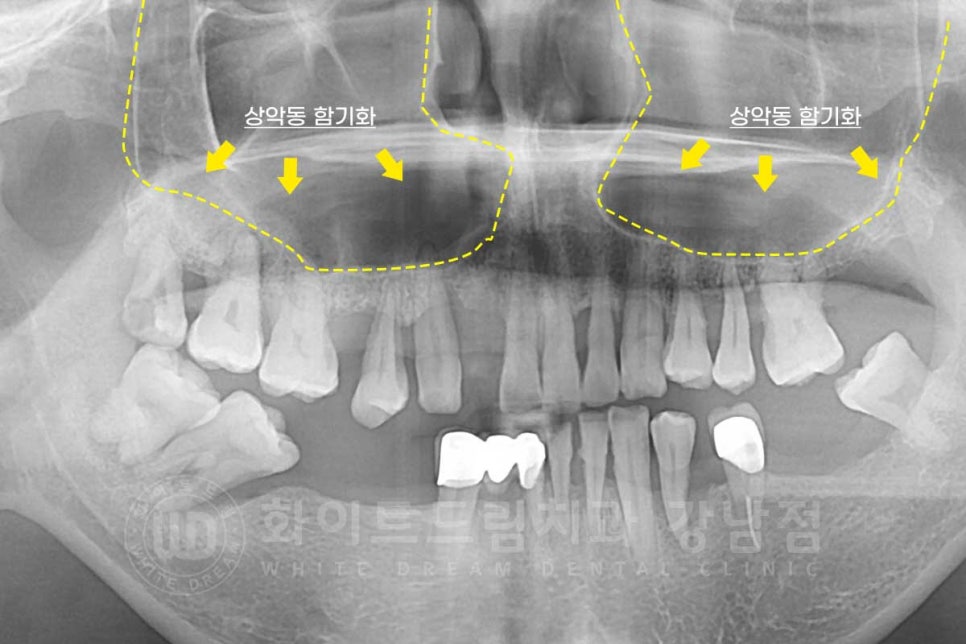

이 중 상악동이 하방으로 많이 내려오는 함기화 현상이 발생한 것이 확인됩니다.

상악동 함기화(sinus pneumatization)란?

상악동이라는 빈 공간이

커지면서 하방으로 내려오는 현상을 말합니다.

어릴 적에는 이 크기가 작다가 보통 노화에 따라서 커지는 경우가 많으며

치아 뿌리 부근까지 내려오게 됩니다.

이 때문에 환자분도 잔존 잇몸뼈가 굉장히 얇아진 상태였기에

상악동을 들어 올린 후 뼈이식을 진행하고, 이후 임플란트를 식립하는 과정이 필요했습니다.